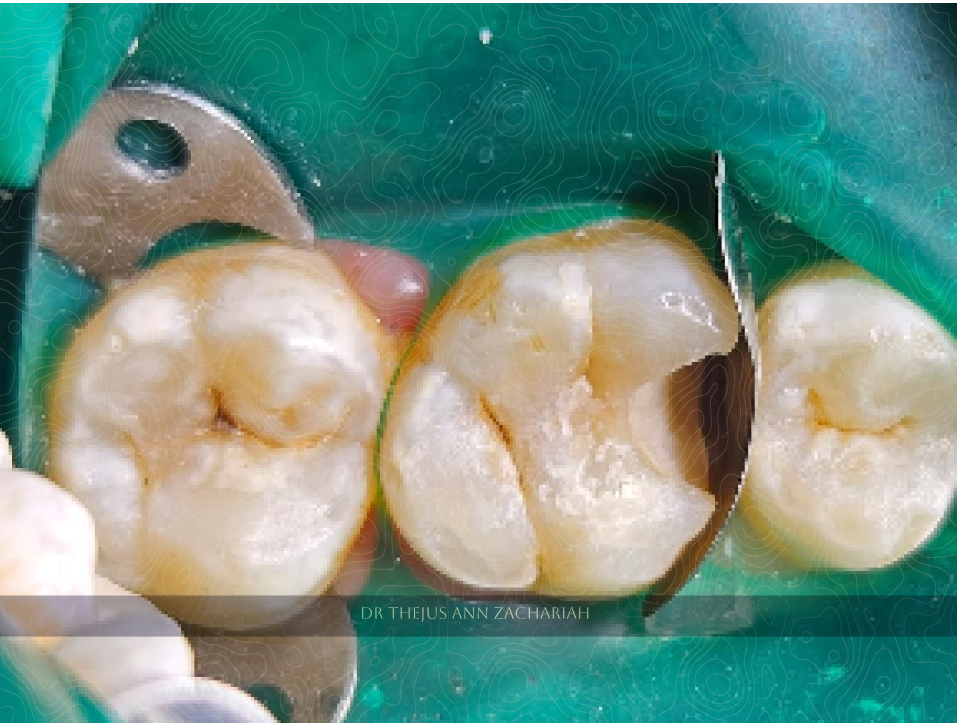

Pin Point Pulp Exposure

alt text

MTA Direct Pulp Capping